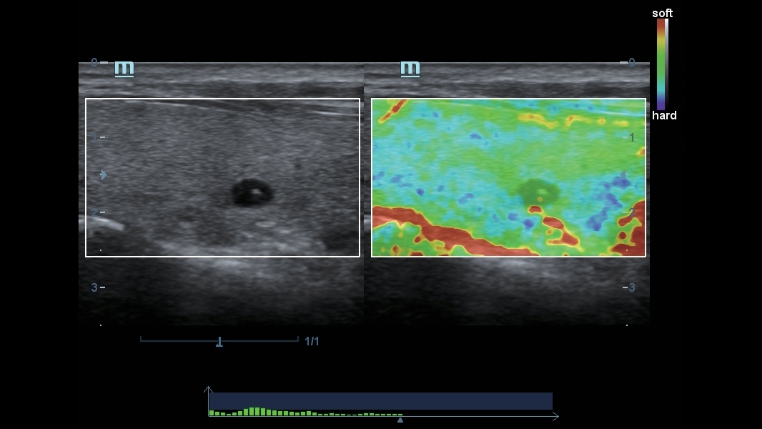

TecnologĂas de obtenciĂłn de imĂĄgenes clĂĄsicas: mejora de la calidad para el diagnĂłstico

Mediante la aplicaciĂłn de tecnologĂas de obtenciĂłn de imĂĄgenes clĂĄsicas, que se migran de sistemas de diagnĂłstico por ultrasonido consolidados, el DC-40 con Full HD le proporciona una mejor calidad de imagen con el grado de detalle que necesita.

- iClear (tĂ©cnica de imagenologĂa con supresiĂłn de manchas)

- PSHI (Phase Shift Harmonic Imaging)

- iBeam: tĂ©cnica de imagenologĂa de composiciĂłn espacial

Transductores ComboWave

En comparaciĂłn con los sensores tradicionales, los transductores ComboWave utilizan un nuevo tipo de material piezoelĂ©ctrico compuesto que optimiza notablemente el espectro acĂșstico y reduce la impedancia acĂșstica. AdemĂĄs de integrarse con la tecnologĂa Ășnica 3T de Mindray, los transductores lineales ComboWave ofrecen un rendimiento sobresaliente con una gran uniformidad y resoluciĂłn de imagen en ecografĂas vasculares, de tiroides, de mama, etc.